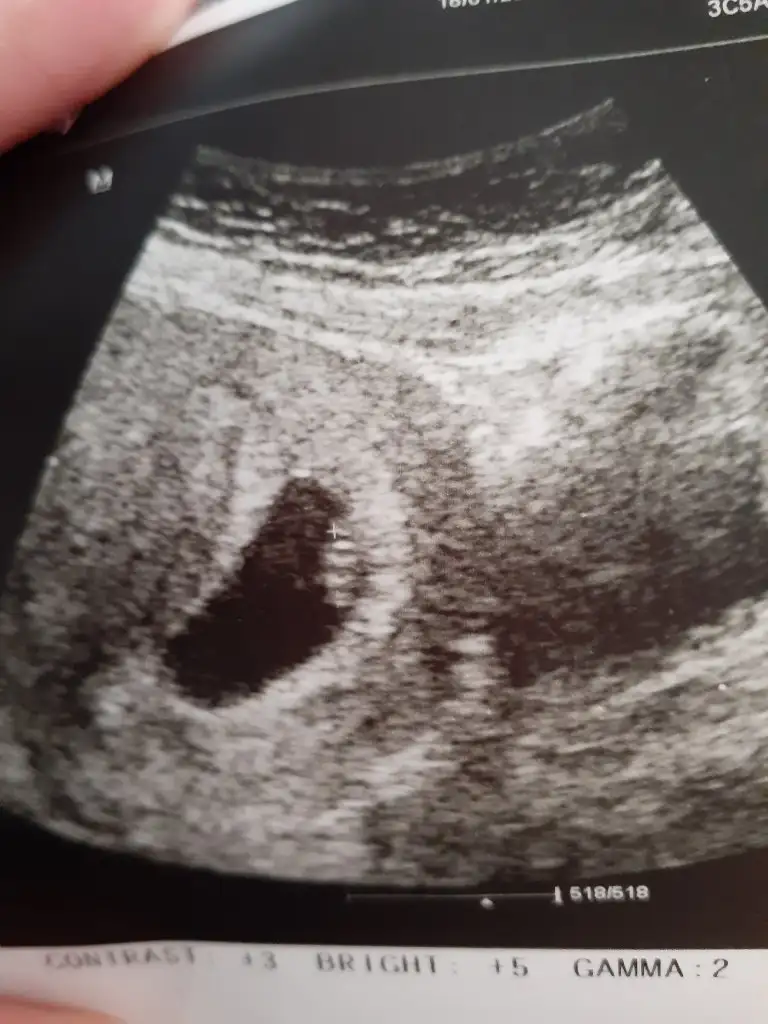

Canım seninki kız teorisine uygun poz vermiş

Ee benimki ne oluyor , burdan anlaşılır mı, sadece keseyi görmüştüm.. Anlayan yorumlasın kızlar haftam 4+6 idi vajinal ultrasondu fark ediyorsa